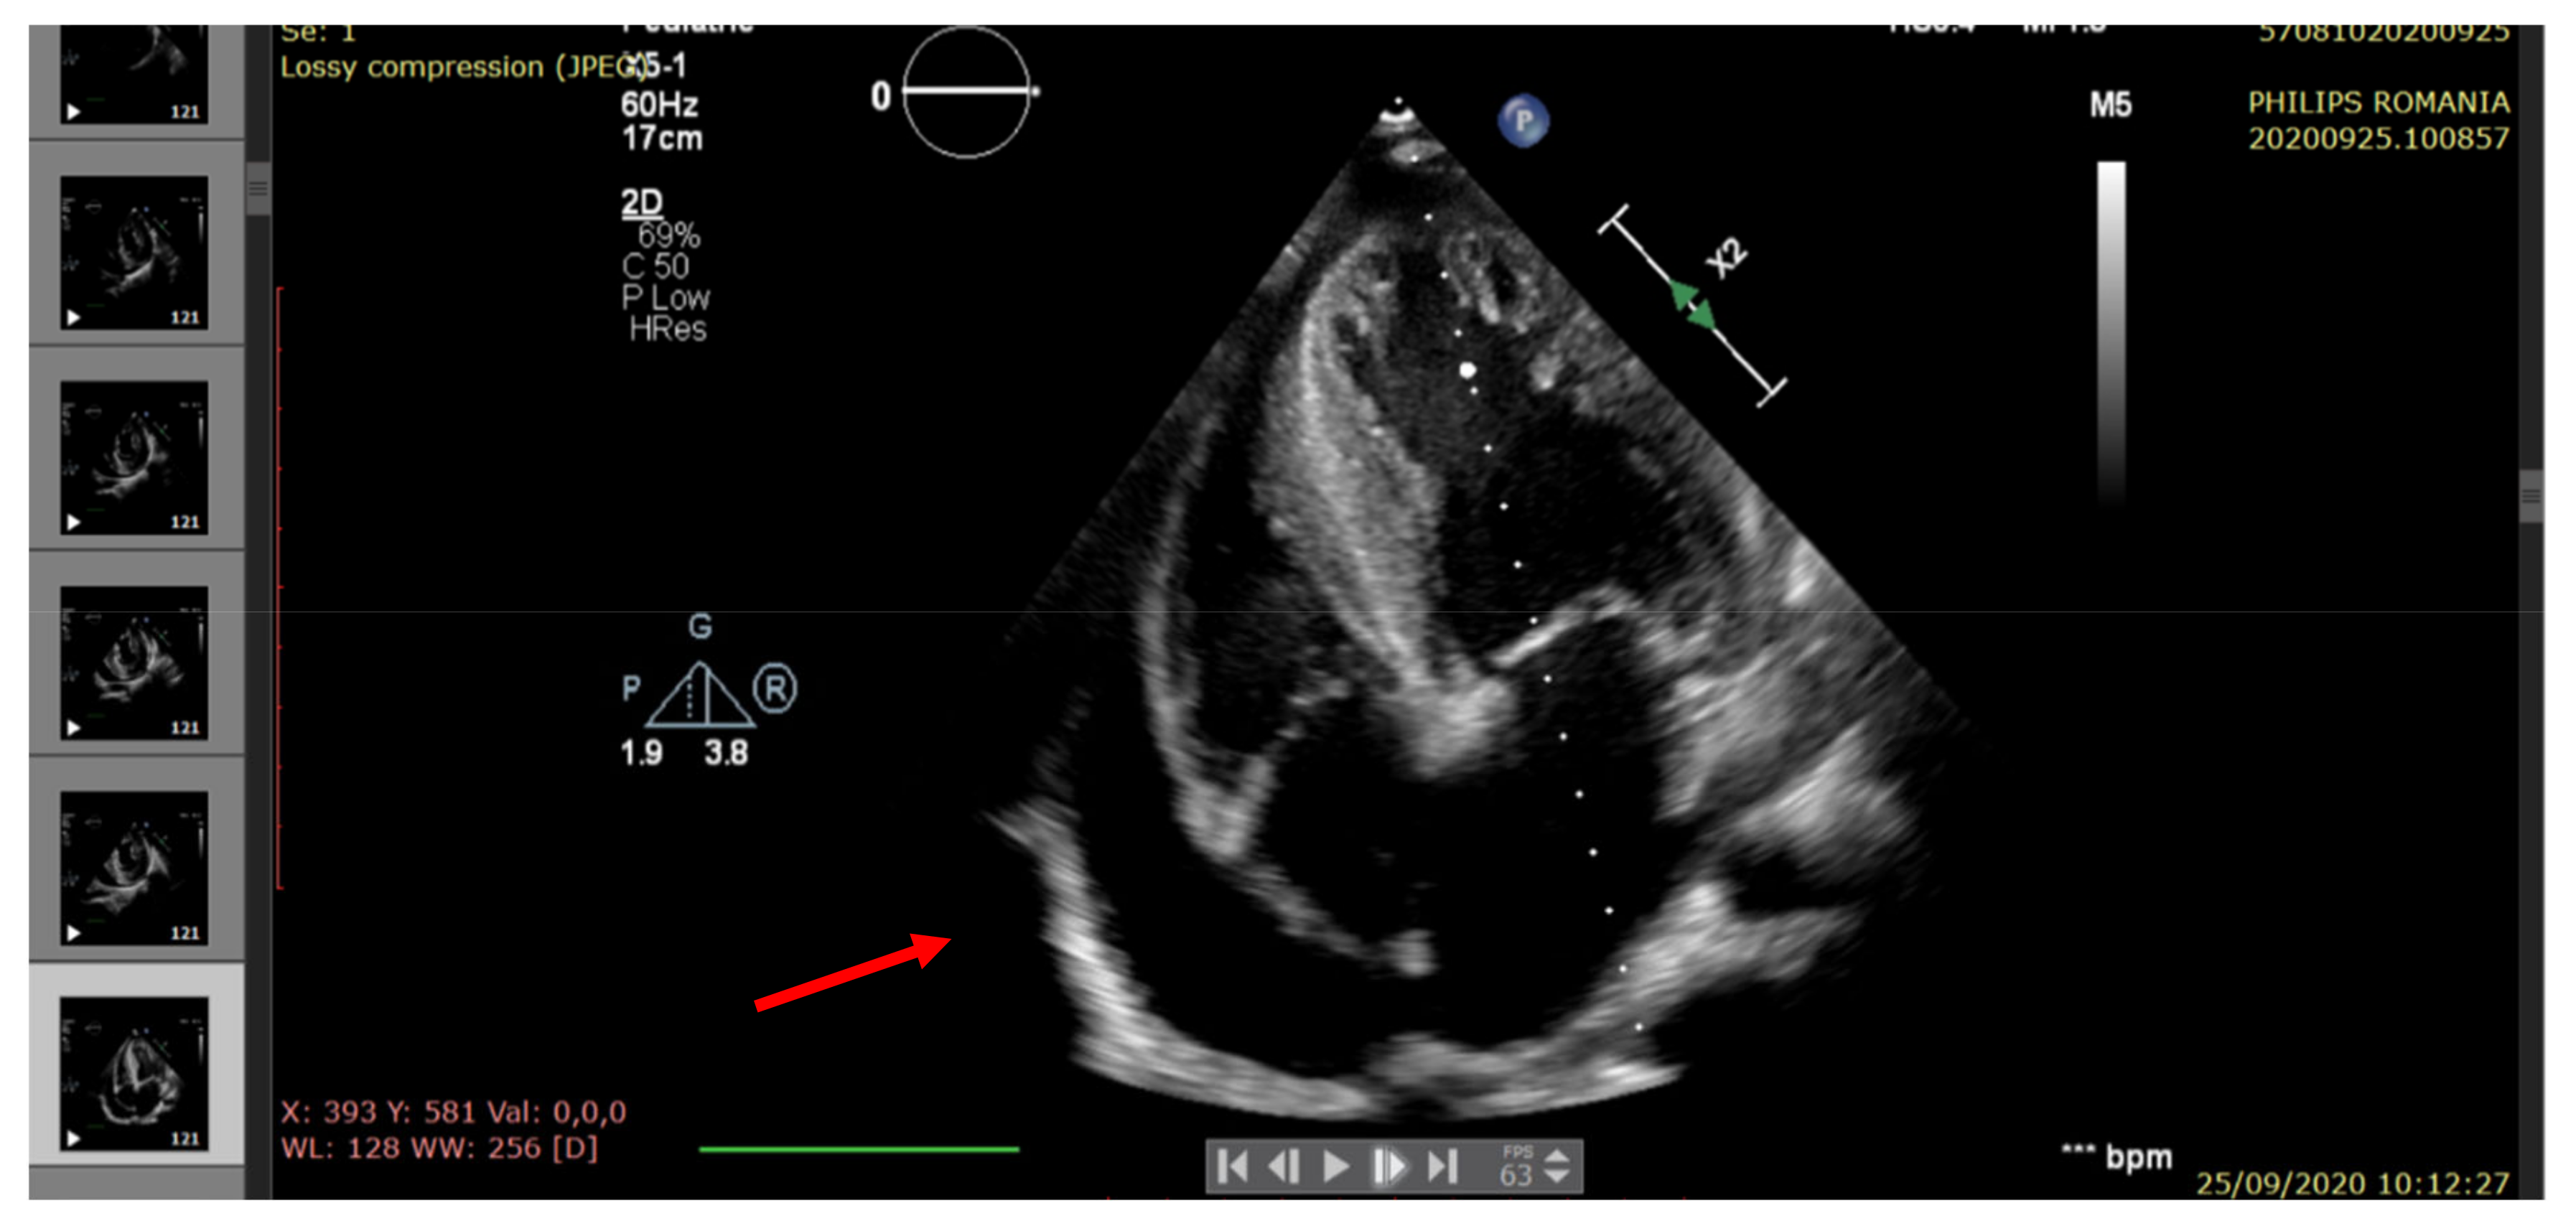

| Pericardial fluid (edge) | <5 mm | Small (6 mm) | Raised (20 mm) | Moderate (14 mm) | Large (22 mm) |

| Pulmonary hypertension (echocardiographic criteria) | Normal | Mild | Moderate | Mild | Moderate/severe |